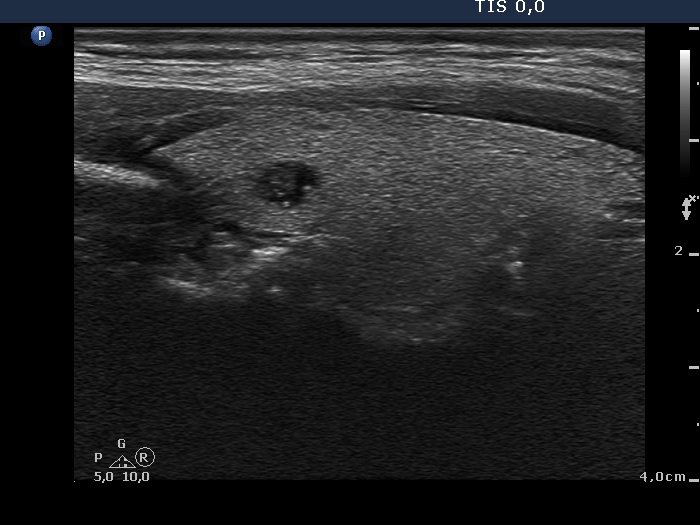

Metastasis of a kidney carcinoma to the thyroid - case 1574 |

Benign hyperplastic nodule (histological diagnosis) - case 1582 |

Both images show one relatively large granule which correspond to punctate echogenic foci.

Parts of the hyperechogenic granules are located in cystic area, while others are found in the solid part of the lesion. The latter might be punctate echogenic foci.